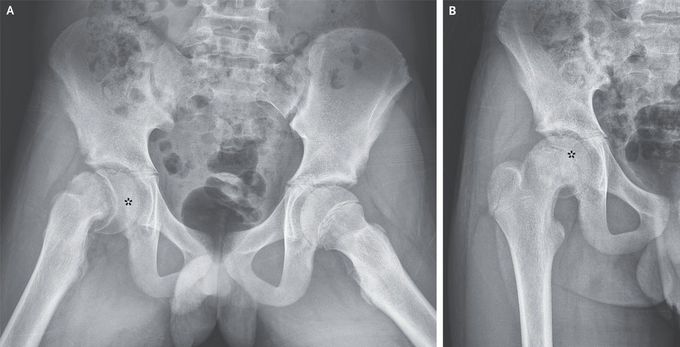

A 12-year-old boy with a history of obesity presented to the orthopedics clinic with a 2-week history of limping and dull pain in the right hip. The symptoms had begun after he had slipped and fallen at school. On physical examination, the patient’s body-mass index was above the 95th percentile for his age. Active and passive ranges of motion of the right hip were limited by pain. Radiographs of the pelvis showed posterior displacement of the right femoral epiphysis, which has been described as resembling a scoop of ice cream slipping off a cone (Panel A, asterisk; frog-leg lateral view), and blurring of the right metaphyseal growth-plate junction (Panel B, asterisk; anteroposterior view). A diagnosis of slipped capital femoral epiphysis was made. This condition is the most common hip disorder in teens. It occurs when the proximal femur displaces anterolaterally and superiorly, which gives the appearance of posterior and inferior displacement of the epiphysis. The condition is associated with obesity but not typically with preceding trauma, as occurred in this case. In situ fixation of the right hip was performed. At a 9-month follow-up visit, the patient’s symptoms had resolved. A repeat radiograph of the pelvis showed union of the right hip without slippage on the contralateral side.